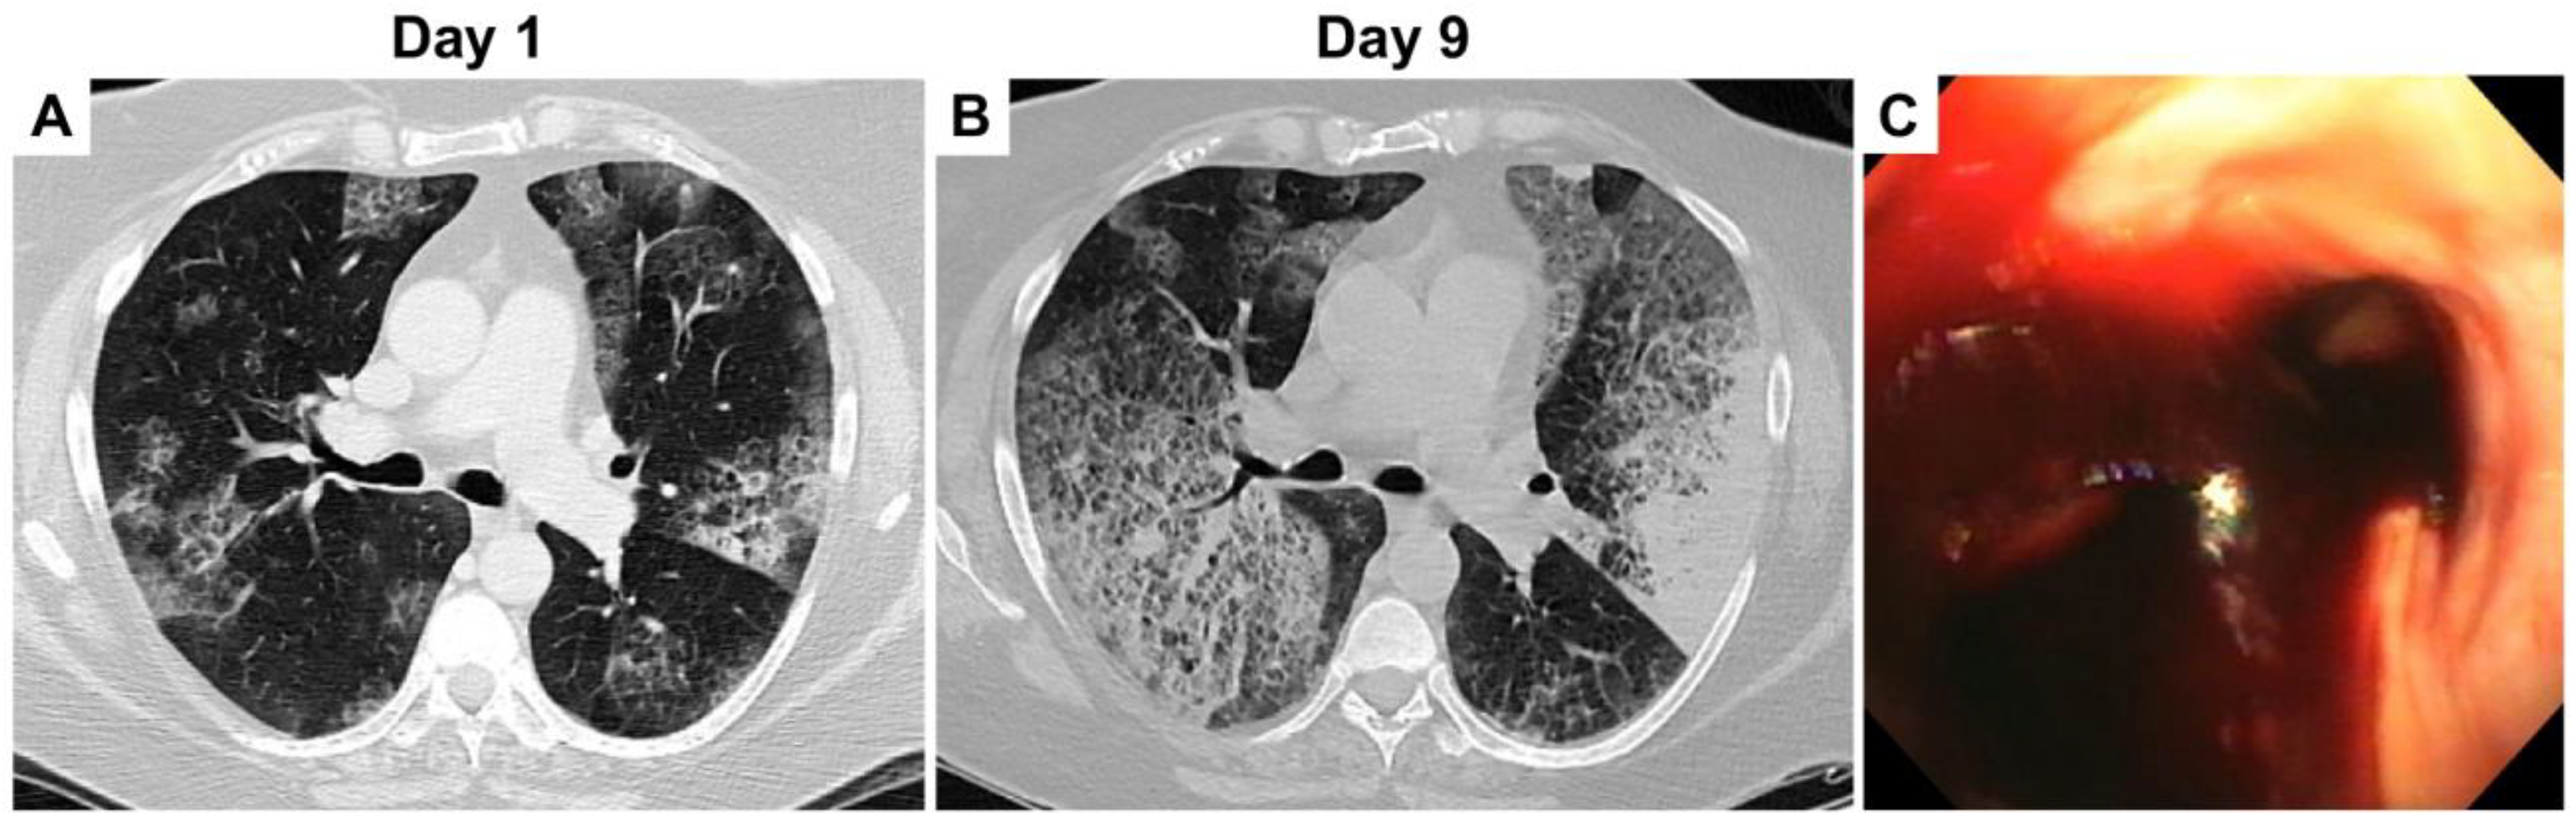

A 64-year-old female with moderate chronic obstructive pulmonary disease (COPD) was treated by her primary care provider with a 5-day-course of azithromycin for one week of hemoptysis. Persistent hemoptysis despite outpatient antibiotic therapy prompted admission to the emergency department (ED). Her chronic therapies included tiotropium bromide 10 mcg inhaler daily, and mometasone furoate and formoterol fumarate dihydrate 200-5 mcg/act inhaler 2 puffs twice daily. The patient did not have fever, chills, hematuria, epistaxis, and bleeding gums. Her blood pressure was 149/63 mmHg, heart rate 105 bpm, respiratory rate 20 bpm, and temperature 98 °F. The oxygen saturation was in the high 80s on room air. Admission lab results included a white count of 8.9 × 103/µL (ref. range: 4.31-10.16 × 103) with a normal differential, hemoglobin 10.6 g/dL (ref. range: 11.5-15.4), platelets 236 × 103/µL, and normal complete metabolic panel. C-reactive protein and sedimentation rate were 7.3 mg/L (ref. range: < 3) and 11 mm/hour (ref. range: 1-20), respectively. Faint bilateral opacities predominately in the upper lung fields were present on the admission chest X-ray. Bilateral upper lobe ground glass opacities with peripheral sparing, and several additional patches of ground glass opacities in the right middle lobe and bilateral lower lobes were noted on chest computed tomography (CT) (Figure 1A). Suspicion of evolving diffuse alveolar hemorrhage prompted serological testing for autoimmune diseases and vasculitides (complement C1Q, C3, C4, lupus anticoagulant, β2-glycoprotein antibody, cardiolipin antibody, anti-DNAse B antibody, histone antibody, anti-nuclear antibody, glomerular basement membrane antibody, anti-neutrophilic cytoplasmic antibody, rheumatoid factor, IgA levels). The results of these tests were negative. INR and PTT were 1.03 (ref. range: 0.84-1.19) and 29 s (ref. range: 23-37), respectively. Bronchoscopy demonstrated clotted blood at the carina and within both major bronchi (Figure 1C). Bronchoalveolar lavage (BAL) was performed with serial aliquots; the degree of noted blood was similar in all containers. The BAL specimen grew only two colonies of unspeciated Bordetella and were negative for malignancy, viruses, fungi, Legionella, and acid-fast bacilli. Synchronous blood cultures were negative. Following the bronchoscopy, empiric pulse dose steroids were initiated with 1 g of methylprednisolone for 3 days.

Figure 1.

(A) Day 1, lung view on chest CT showing bilateral pulmonary ground glass opacities. (B) Day 9, worsening bilateral ground glass opacities on repeat chest CT. (C) Bronchoscopy showing clotted blood at the carina.

Empiric i.v. azithromycin 500 mg was initiated given an unknown etiology and the few colonies of Bordetella identified on BAL fluid. Repeat bronchoscopy identified active bleeding from both upper lobes. Repeat BAL of the right upper lobe grew 4+ Bordetella. Microbiological speciation was requested provided this significant increase in bacterial growth. She was started on broad spectrum antibiotics with i.v. cefepime 2 g every 12 h and vancomycin 15 mg/kg every 12 h. Over the next two days, the patient’s pulmonary hemorrhage persisted. Worsening bilateral ground glass opacities were noted on repeat chest CT (Figure 1B). Pulmonary angiogram identified bleeding from the bronchial arteries within both upper lobes, which were embolized. Despite these interventions, pulmonary hemorrhage continued, requiring additional bronchoscopies for evacuation of blood in both the upper and lower lobes. The patient deteriorated, with hemodynamic shock refractory to vasopressor therapy. Repeat bronchoscopy now grew 5+ Bordetella. Repeat blood cultures were also positive for Bordetella. At this time, the patient’s family elected to stop life support and the patient died. The next day postmortem, speciation from the bronchoscopy and blood cultures resulted as Bordetella bronchiseptica. The susceptibilities of the organism are summarized in Table 1.